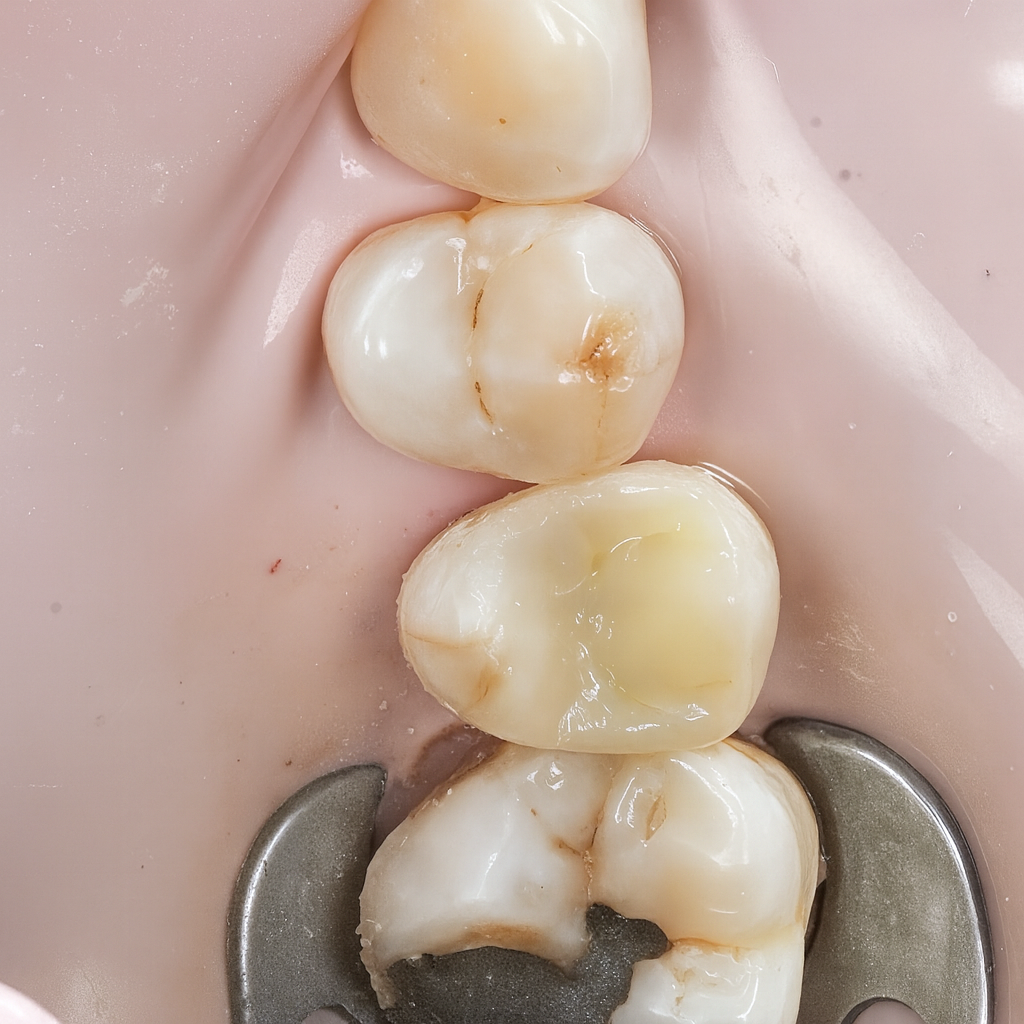

Diagnosis

Clinical and radiographic exam confirmed adjacent Class II carious lesions affecting both teeth, with secondary caries beneath existing composite and defective margins.

Rubber dam isolation achieved using clamp stabilization to maintain a dry and clean operative field – essential for adhesive dentistry (Fig 1–2).

Defective composite and caries were removed in a controlled manner preserving sound enamel walls. Teflon floss ties and wooden wedges used for separation and gingival retraction (Fig 3–6).

- Preoperative occlusal view showing defective composite & caries

- Rubber dam isolation

- Initial caries exposure and removal